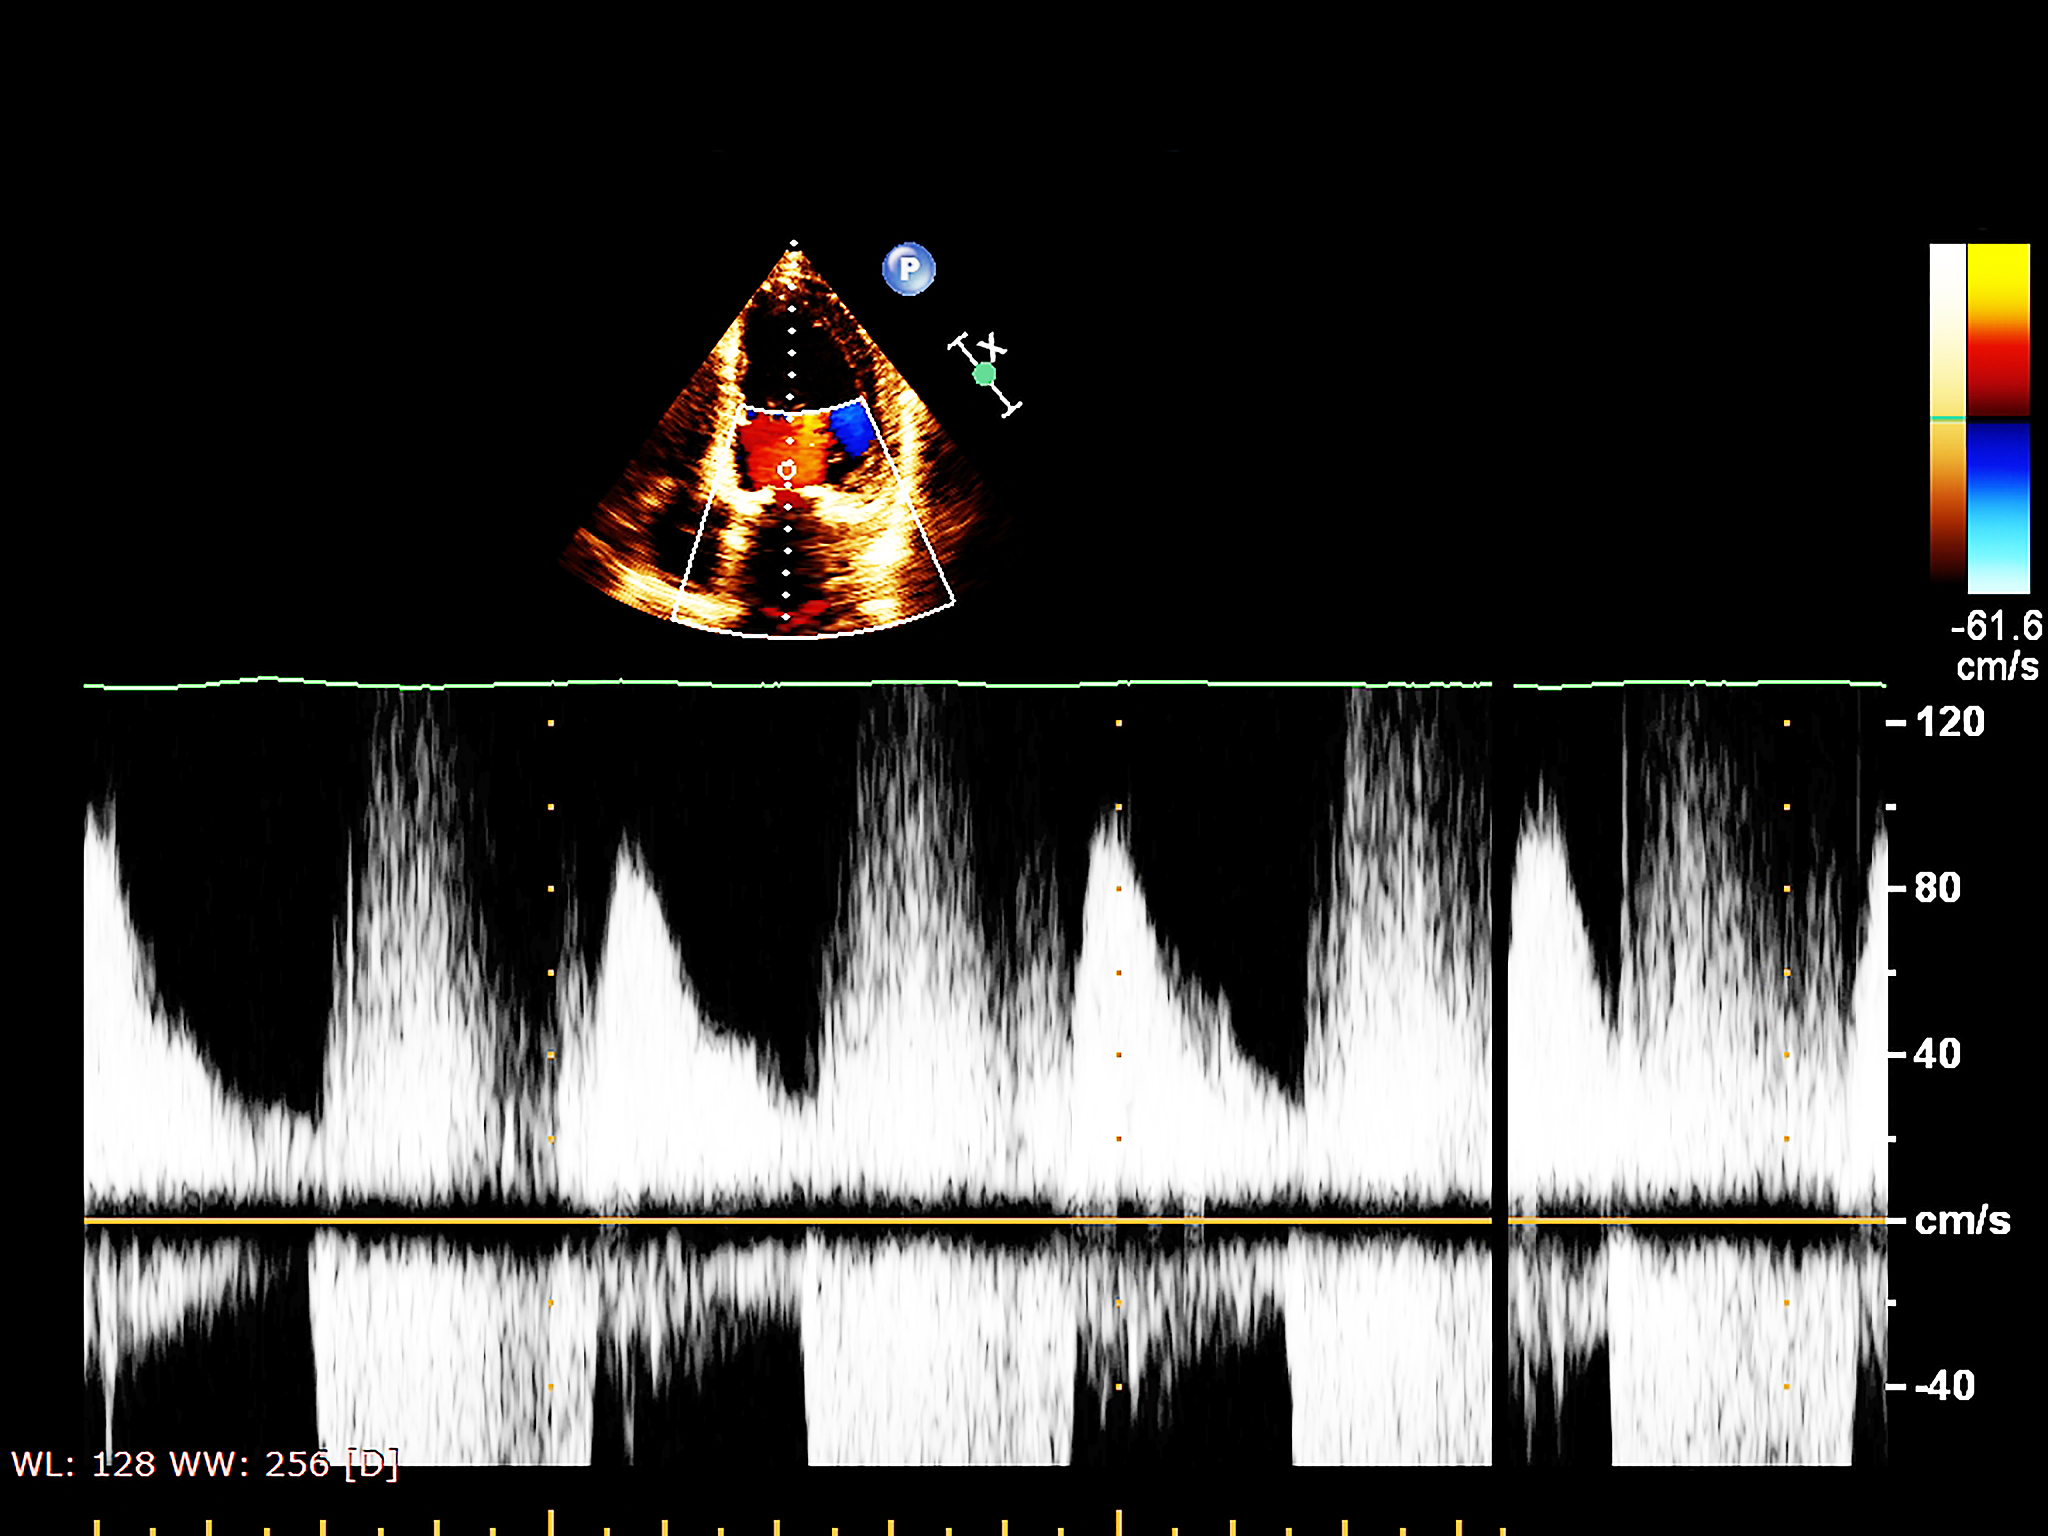

超声波在工业、医学、生物学等领域都有广泛应用。在医学中,超声波可以用于成像、检测和治疗。超声成像是通过超声波在人体内部的不同组织和器官之间的反射来获得图像的。超声检测则是通过超声波对物质的穿透和散射来检测物质的缺陷、材料性质等信息。而超声治疗则是利用超声波的热效应和机械效应来治疗肿瘤、疼痛等疾病。